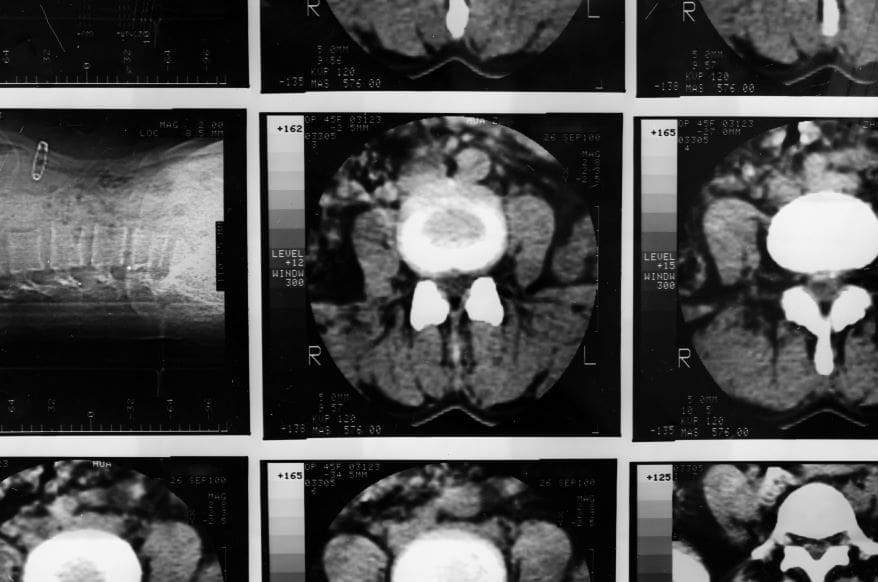

Researchers at the Washington University School of Medicine in St. Louis have developed a non-invasive treatment technique of nasal nanodrops. They collaborated with partners at Northwestern University in order to create it. The strategy is intended to treat one of the most severe and rapidly spreading forms of brain cancer available. Their method uses nanoscale structures designed in order to deliver potent anti-tumor substances directly into the brain through simple nasal nanodrops. In experiments with mice, this delivery system successfully targeted glioblastoma, a form of brain cancer. It also boosted the brain’s immune defenses. The technique is less invasive than many other therapies currently under investigation.

- Studying the unique characteristics as well as vulnerabilities of Glioblastoma and other brain tumor types that can be targeted by the nanoscale drug delivery system

- Investigating the mechanisms by which the nanoscale structures can modulate the tumor microenvironment and also strengthen the brain’s immune defenses